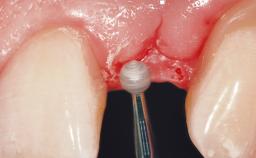

A 36-year-old female patient was referred for the replacement of the upper left central incisor (tooth 21), which had fractured. Although the tooth had been asymptomatic for many years, the crown began to loosen, at which time she presented to her dentist for an assessment. Teeth 21 and 22 had both been endodontically treated many years previously. She was a healthy individual and a non-smoker.

On examination, the patient had a low lip line and only displayed the coronal half of the anterior teeth when smiling.